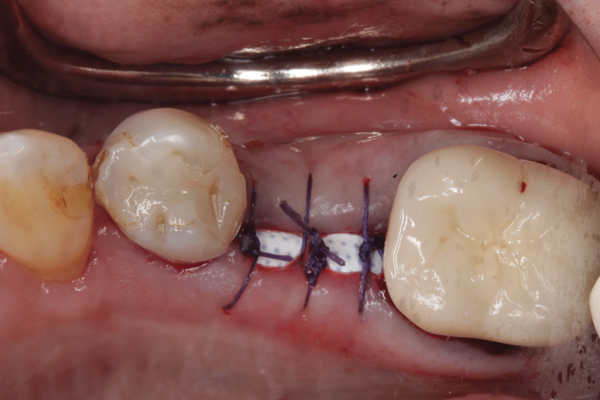

Fig 22. Bone graft was placed in the socket and a d-PTFE barrier was used to cover the graft. The bone graft material was placed beyond the alveolar housing to accommodate shrinkage of graft material and to facilitate attaining a wide alveolar ridge. The barrier was removed after 5 weeks.

Figure 22

Fig 23. Implant inserted in a regenerated ridge after 6 months healing.

Figure 23